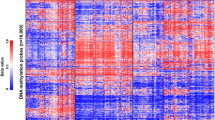

Oligonucleotide-based microarrays are slowly emerging as the platform of choice for genome-wide analysis due to their high-throughput and high-resolution (Bignell et al. 2004; Friedman et al. 2006; Janne et al. 2004; Ming et al. 2006; Zhao et al. 2004). Further, single nucleotide polymorphism (SNP) based oligonucleotide microarrays allow for the detection of copy number neutral loss of heterozygosity (LOH) events that are prevalent in cancers (Langdon et al. 2006; Maris et al. 2005). In the present study, we utilized high-density SNP oligonucleotide arrays to determine the extent of 22q11.2 deletions involving INI1 in five patients with rhabdoid tumors. As most array platforms avoid LCR regions when designing probes due to a lack of localizing specificity, we utilized fluorescence in situ hybridization (FISH) as well to further characterize the deletions. Two of the patients had initial genetic evaluations due to phenotypic features seen in DGS/VCFS. The remaining three infants had two or more primary tumors, consistent with a genetic predisposition to malignancy. Such approaches provide a rapid diagnostic tool for patient management. Furthermore, the high density of probes allow for a more precise localization of deletion breakpoints which may lead to a better understanding of the mechanisms responsible for the deletions in patients with congenital disorders and malignancies.

High-density oligonucleotide array analysis of DNA from the blood using the 50 K Xba SNP chip confirmed the 22q11.2 deletion. Based on the LCR coordinates (Supplemental Table 1), the proximal breakpoint localized to LCR region D, which is the distal end of the typical DGS/VCFS deletion region. The distal breakpoint was in LCR G (Supplemental Table 2). This deletion is approximately 2.7 Mb in size. The oligonucleotide analysis of the blood DNA also revealed a duplication of 20p12.1. There are no known genes or polymorphisms in this region, thus the clinical significance is not known. Additional FISH studies of the cell line confirmed the array results, demonstrating loss of one copy of both 45C9 and 61E11 with retention of both copies of C2C9 and 20P18 (Fig. 3).

Analysis of blood and tumor DNA using the 50 K Xba chips demonstrated a 2.7 Mb germline deletion in chromosome 22q11.2 with breakpoints in LCRs D and G, similar to patient 1 (Supplemental Table 2). In addition to the abnormalities on chromosome 22, the SNP array analysis revealed regions of LOH present in both the tumor and blood in 2p16.3, 3p12.1–12.2, and 3q21.3–22.1. In addition, both a duplication of 6p21.32 and a more proximal deletion in 22q11.21–11.23 were present in both the tumor and blood samples. These abnormalities were in regions with previously described polymorphisms and are thus presumed to be incidental findings (Conrad et al. 2006; Hinds et al. 2006; McCarroll et al. 2006; Sebat et al. 2004; Sharp et al. 2005; Tuzun et al. 2005). Duplications were also found in the tumor DNA in 1p31.1 and 3q25.2. In both instances, although the changes did not meet criteria to be considered significant in the blood sample, there were similar changes present. The only tumor specific change was a deletion in 4q34.3. There are no currently known genes in this deleted region.

As shown in Fig. 3, FISH analysis was consistent with the array results, which demonstrated deletions of 45C9 and 61E11 and retention of both copies of C2C9 and 20P18.

High-density oligonucleotide array analysis of the tumor DNA using the 50 K Xba chip revealed a deletion of 22q11.2 in which the region that included INI1 was homozygously deleted. The breakpoints for the tumor deletion were localized to LCR region E and proximal to LCR H with an approximate size of 1.7 Mb. Analysis of the blood DNA on the 250 K Nsp array revealed a smaller 1.5 Mb deletion of chromosome 22 including the INI1 locus. In this instance the breakpoints were localized between LCR regions E and F proximally (proximal to BCR) and between LCR regions G and H distally (proximal to 20P18).

Further FISH analysis of his blood to confirm the array results revealed two copies of 61E11 and 20P18, representing the limits of the germline deletion (Fig. 3). A population of tumor cells (36/100) demonstrated loss of one copy of 20P18 with retention of EWS, suggesting a larger deletion in the tumor. Based on the retention of two copies of 297M14 in the tumor DNA by FISH and the deleted SNP coordinates, the distal extent of the larger tumor deletion was confirmed to be proximal to LCR H.

Analysis of the blood DNA with the 250 K Nsp chip revealed a 0.9 Mb deletion with breakpoints within LCR region F and between LCR regions G and H in a known recombination hotspot. These results were confirmed by FISH, which revealed one copy of 20P18 but two copies of 297M14. Both BCR and 61E11 were present in two copies in the blood sample (Fig. 3).

FISH and high-density oligonucleotide analysis were performed on both the normal brain and brain tumor tissue from the autopsy. FISH analysis of the tumor DNA revealed homozygous loss of INI1. Analysis of the normal brain tissue revealed a deletion of one copy of INI1 with retention of both BCR and 20P18 (Fig. 3). These results were subsequently confirmed on an established lymphoblast cell line.

The 250 K SNP array demonstrated a germline deletion approximately 1.0 Mb in size in the normal brain with the same 1.0 Mb deletion (homozygous deletion) in the tumor tissue (Fig. 5). The breakpoints were found to be in identical locations for both the normal brain and tumor tissue, within LCR region F and between LCR regions G and H, respectively. Interestingly, analysis of the tumor DNA revealed loss of heterozygosity for the entire chromosome 22 suggestive of loss and duplication of the deleted homologue.

CNAG output for chromosome 22 of patient 5. Plot analysis demonstrates a decrease in the log2R ratio for both the normal brain and tumor samples in the same region of chromosome 22 (including INI1). The magnitude of the decrease in log2R ratio for the tumor DNA is about twice the magnitude of the decrease found in the normal brain DNA, consistent with loss of one allele in the blood and loss of both alleles in the tumor